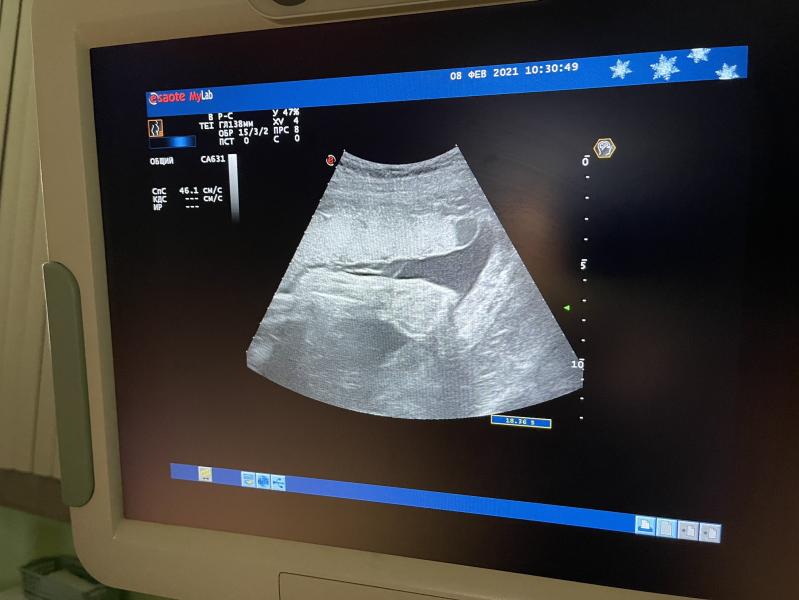

Третий скрининг пройден) с сыном все хорошо, опережает развитие на неделю, весит уже 2100. Однократное обвитие, но ничего ещё размотается) лежит уже головой вниз) лицо не дал сфоткать, смущался и буянил)

Через неделю пойду платно на скрининг, потому что это все, что мне в ЖК сказали) скрининг шёл ровно 5 минут🤔